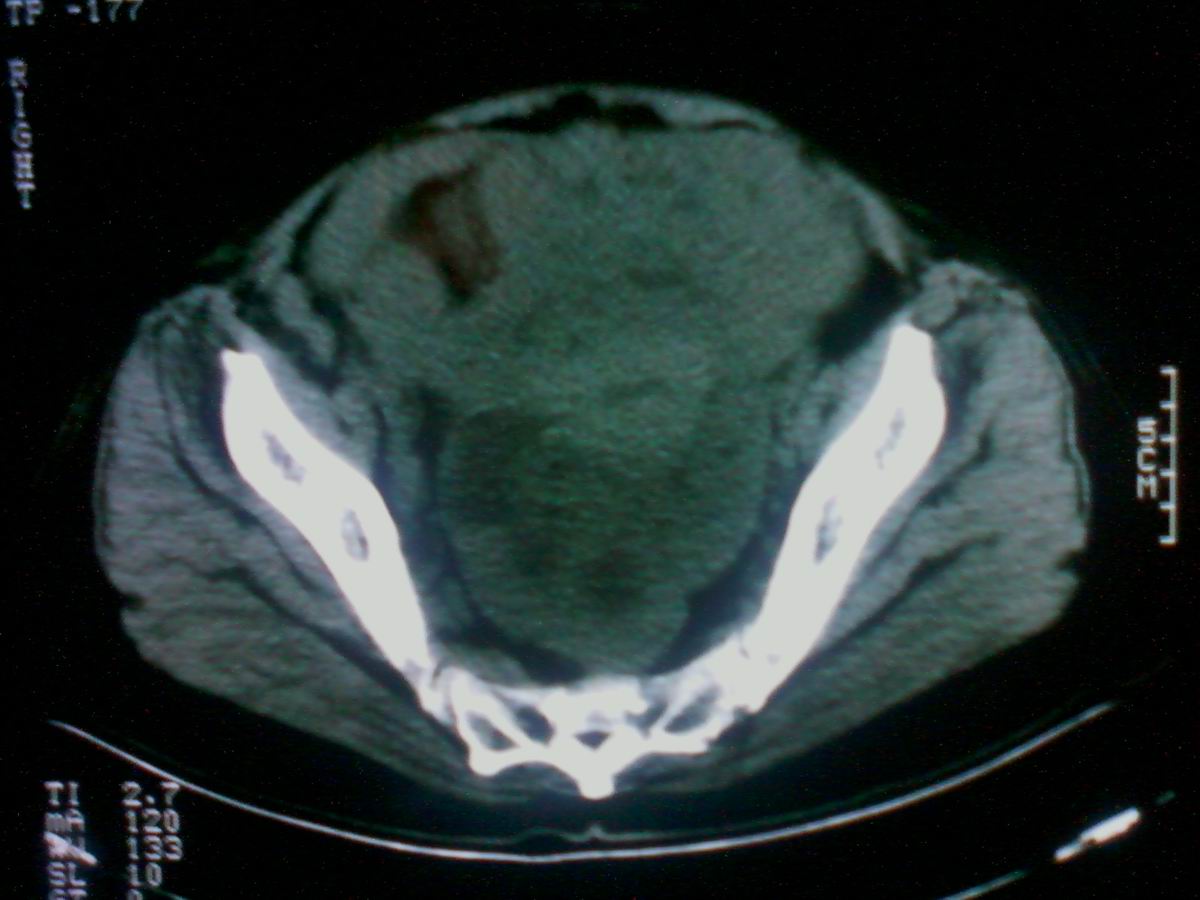

标题: CT25799:女性患者,45岁,腹胀,上腹部疼痛来诊,B超示盆腔 [打印本页]

标题: CT25799:女性患者,45岁,腹胀,上腹部疼痛来诊,B超示盆腔

考虑卵巢癌伴腹水

1)考虑卵巢恶性肿瘤。2)腹水。